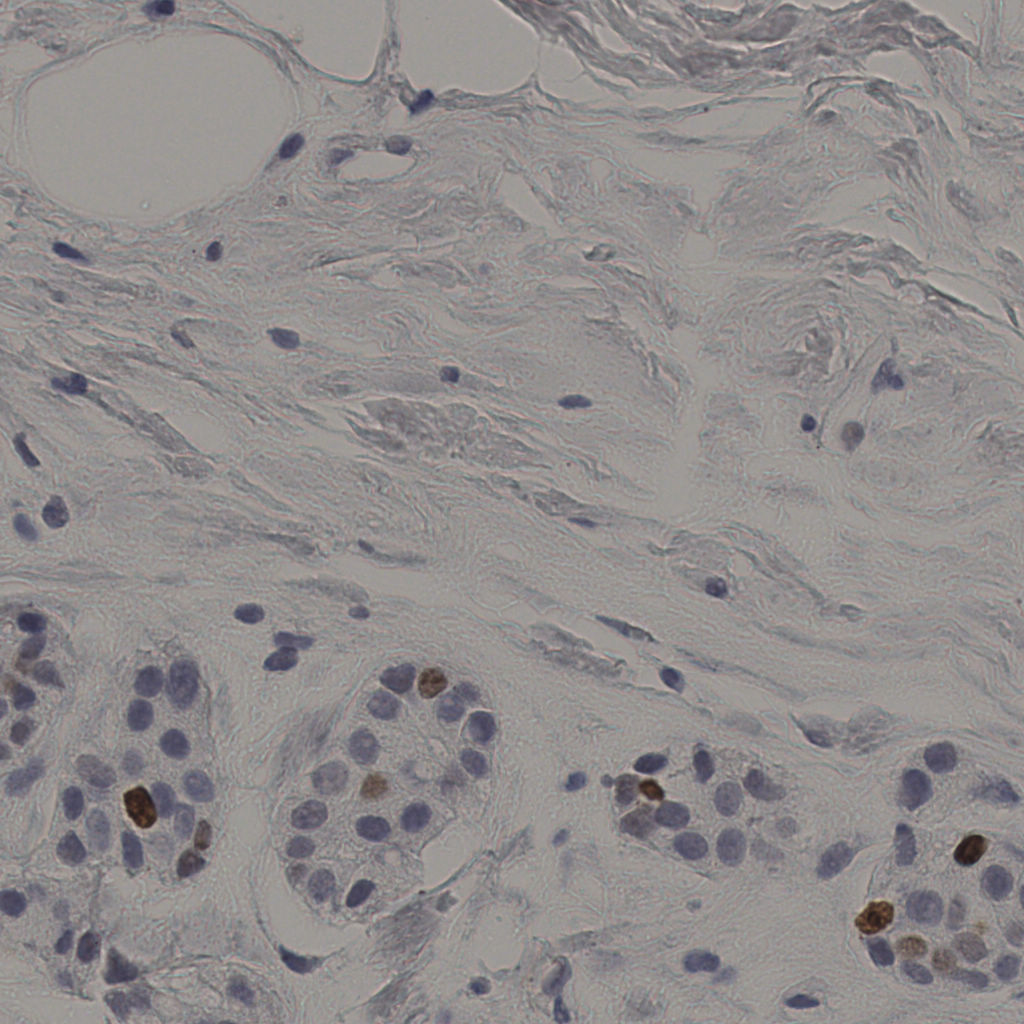

缩略图

标记后

标记前